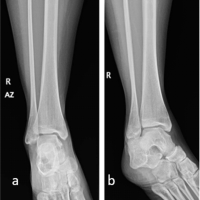

Definitive fixation was achieved by utilizing multiple suture tape bridges and fixation with bone anchors to reinforce the failed dorsal carpal and carpometacarpal ligaments in an internal bracing method. This is an augmentation method that uses high-strength non-absorbable suture tape to overlay the ruptured ligaments and provide support during ligamentous healing and scar formation. The first bone anchor (3.5-mm DX SwiveLock SL; Arthrex, Naples, FL) was placed in the hamate. This was attached to a suture tape (FiberTape; Arthrex, Naples, FL) that was subsequently anchored into the capitate with one limb and a second limb anchored to the triquetrum, as shown in Fig. 3.